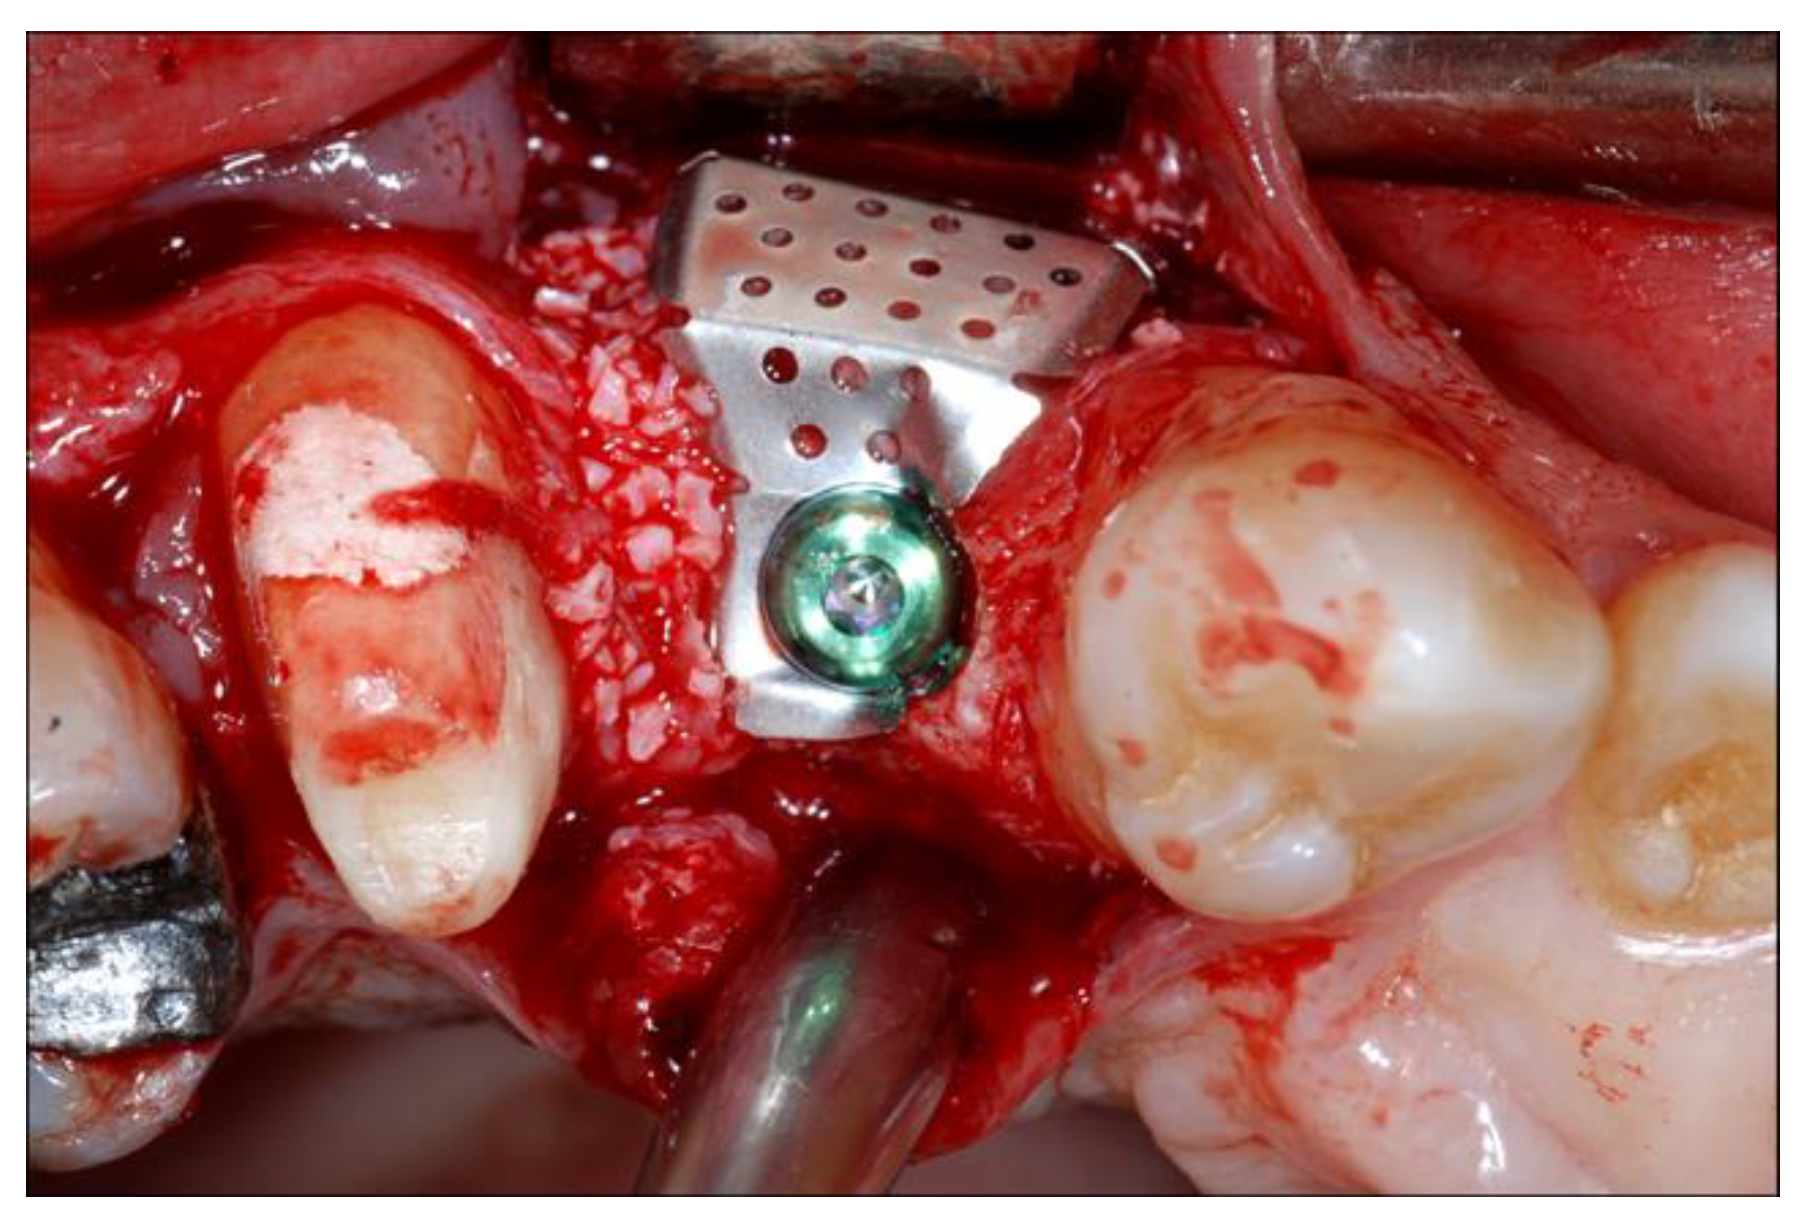

2.4. Surgical Phases

2.5. Re-Entry Surgery and Prosthetic Phases